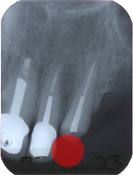

Eine 60 Jahre alte Patientin verlor im Oberkiefer links hinter dem Eckzahn einen vereiterten, beherdeten Prämolaren (Abb. 1, Pfeil) (Endodontie). Als die Eckzahn-Stiftkrone auch noch brach (Abb. 2, roter Kreis), entstand sowohl ästhetisch wie funktionell eine ungemütliche Situation.